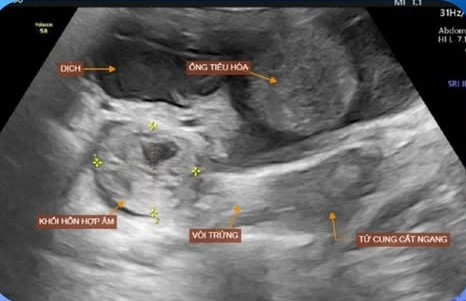

Tại đây, các bác sĩ khám ấn đau vùng hạ vị. Xét nghiệm có biểu hiện hội chứng nhiễm trùng. Siêu âm ổ bụng có hình ảnh khối hỗn hợp âm cạnh buồng trứng phải (theo dõi chửa ngoài tử cung vỡ chưa loại trừ vỡ nang Degraff), dịch tự do ổ bụng. Tuy nhiên, xét nghiệm: Beta hCG <2,3 U/l nên loại trừ được nguyên nhân do chửa ngoài tử cung vỡ, mà chẩn đoán chẩn đoán xác định vỡ nang Degraff.

| Kết quả siêu âm của bệnh nhân. Ảnh BVCC |